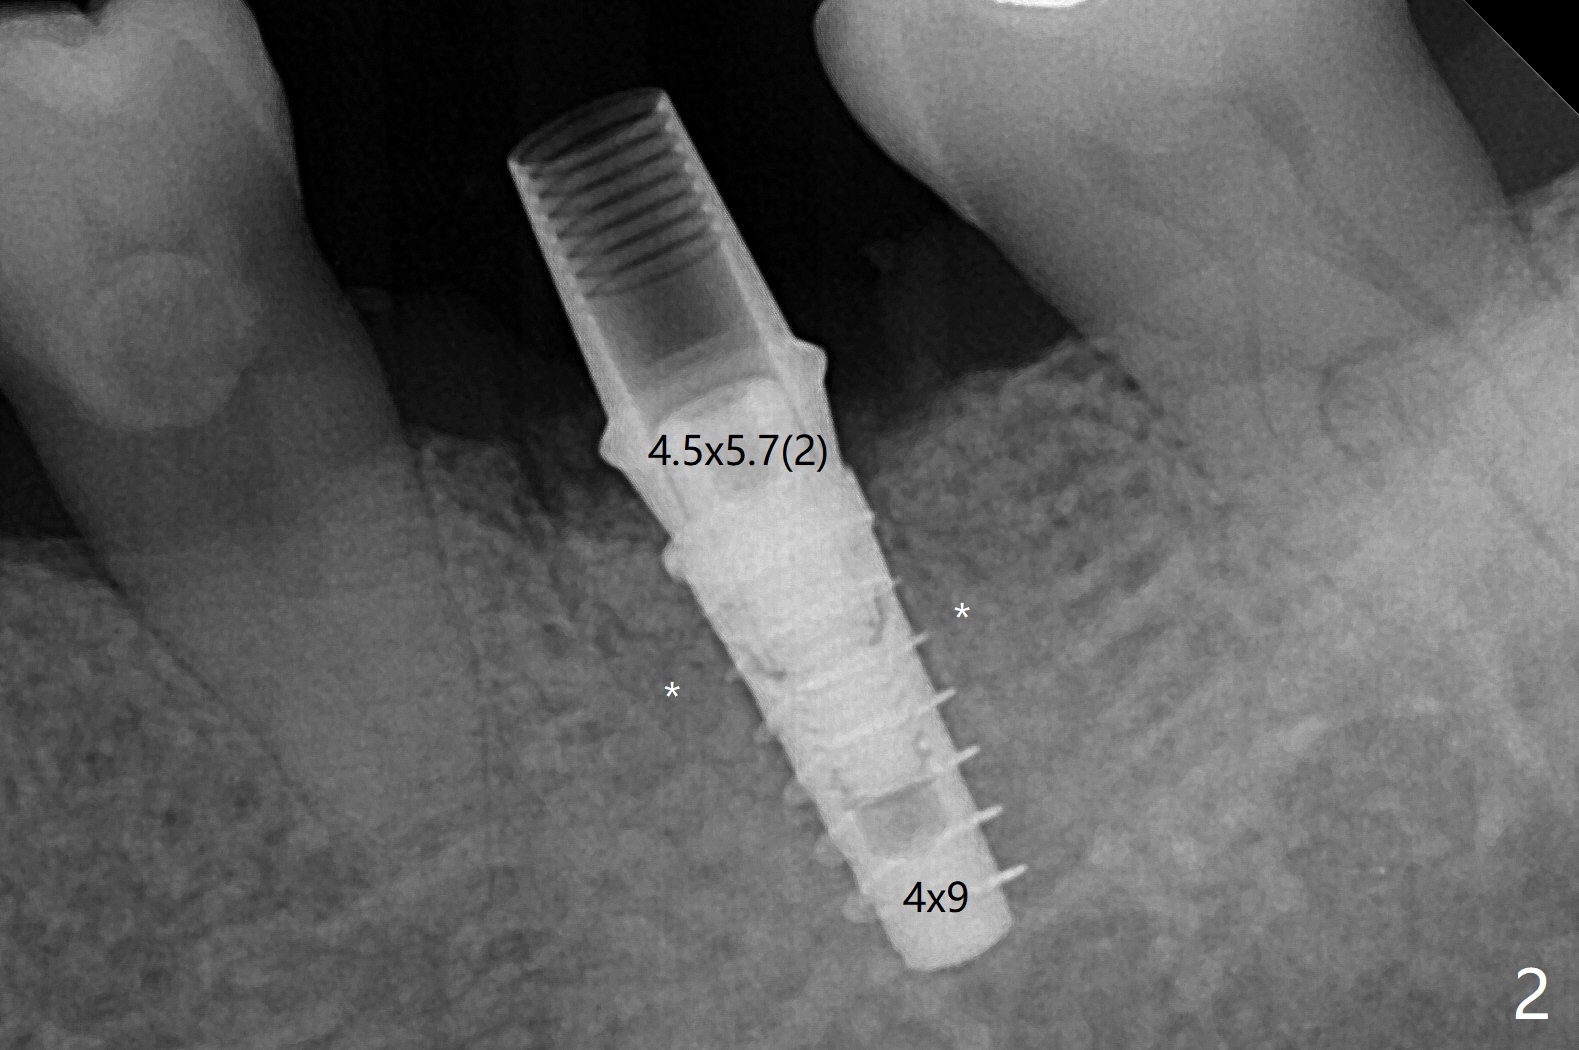

左下第一磨牙拔除后,放置导板,最细钻头到深度,没有偏移: 在中隔正中(图一),细短植体植入后基本保持在中隔之中(图二),扭力~30Ncm,在近中,远中剩余牙槽窝植骨后(图二:*),安置修复基台。制作临时牙冠后,在基台周围再次放置骨粉(图三)。术后7天牙周敷料脱落,12天复查时,临时牙冠周围软组织(角化龈,龈乳头)正常(图四)。